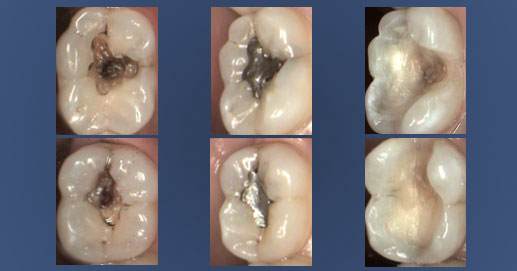

La tecnica di enucleazione.

L’otturazione in amalgama viene rimossa come se si togliesse la pietra da un anello, cioè intera. Grazie a questa tecnica, l’amalgama viene rimossa intera nel 70% dei casi, mentre nel restante 30% si combina l’approccio iniziale con il “Protocollo Svedese”, ovvero si toglie l’amalgama restante per frantumazione in pezzi grossolani.